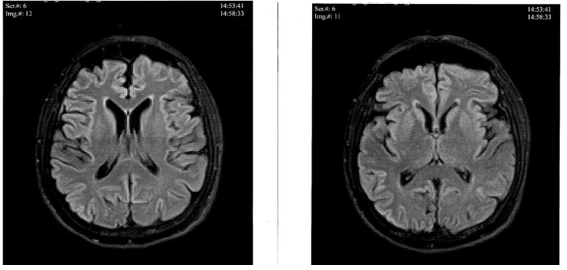

Doppler sonography of brain vessels found no significant changes. Electroencephalography (EEG) revealed abnormal recordings with generalized slow theta waves (5-7Hz). Permanent theta waves, single polymorphic delta waves and high amplitude triphasic sharp waves were registered in the frontotemporal regions bilaterally, predominantly on the right (Figure 2A). During admission, extensive diagnostic workup was performed, including peripheral blood, kidney and liver function, and thyroid hormone levels, all of which were within normal limits. Erythrocyte sedimentation rate and C-reactive protein (CRP) were elevated (52mm/h and 8.7mg/l respectively) (Table 1). The control test four days later registered sedimentation rate 33mm/h and CRP 4.9mg/l. Three weeks after an immunosuppressive treatment with methylprednisolone the sedimentation rate was 78.0mm/h and CRP was 16.2mg/l. Vit B12 and folic acid were below the normal limits (159.0pg/ml and 5.61ng/ml) . She was admitted to the department two weeks later because of the progression in behavioral deterioration. Neurological examination revealed no focal neurological signs. Magnetic resonance imaging (MRI) with angiography, performed three months after the initial symptoms, revealed no brain tumor, vascular or inflammatory changes, no hyperintense lesions (Figure 1).

Figure 1 T1w images of MRI performed three months after the initial symptoms. There is no supra- and infratentorial evidence of acute disseminated encephalomyelitis, vasculitis, or neoplasms.